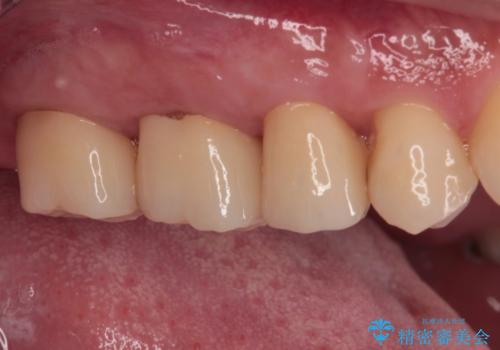

まずは仮歯に置き換え、歯周ポケットを除去するための外科処置(歯肉弁根尖側移動術)を行い、治癒を待ってセラミッククラウンにて補綴治療を行うこととしました。

外科処置後は知覚過敏症状が酷くなることが多いのですが、術後は比較的落ち着いており、スムーズに処置を進めることができました。